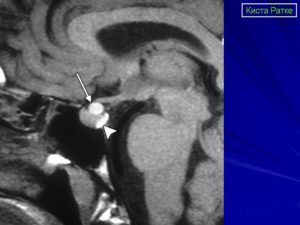

Если предполагается злокачественный характер опухоли, показана консультация онколога. Один из самых информативных методов диагностики – МРТ исследование, которое позволяет дифференцировать кисту, сформировавшуюся в зоне кармана Ратке, от таких патологий, как арахноидальные кисты или аденомы гипофиза (пролактиномы).

На снимке отчетливо видно хорошо отграниченное новообразование кистозной структуры округлой или продолговатой формы иногда с утолщенной стенкой. КТ-томография показывает большую плотность ткани кисты по сравнению с окружающей мозговой тканью.

Магнитно-резонансная томография

Кисты кармана Ратке почти всегда имеют гомогенную интенсивность МР сигнала, в то время как кистозные краниофарингеомы и аденомы с кровоизлиянием имеют гетерогенный сигнал. [9] Уровни жидкости подразумевают кровоизиляние в анамнезе. Хотя кисты кармана Ратке не имеют характерных только для данной нозологии МР признаков. Большинство кист можно отнести к двум группам:

- Кисты кармана Ратке с низкой интенсивностью МР сигнала на Т1 взвешенных изображениях и высокой интенсивностью сигнала на Т2 взвешенных изображениях,

- Кисты кармана Ратке с высокой интенсивностью МР сигнала на Т1 взвешенных изображениях и различной интенсивностью МР сигнала на Т2 взвешенных изображениях

В первой группе содержимое кисты серозное и имеет сигнальные характеристики соответствующие ЦСЖ. Во второй группе содержимое кист богато мукополисахаридами, которые считаются продуктами муцин-продуцирующих клеток в стенке кисты.

Главным методом для обнаружения кисты является магнитно-резонансная или компьютерная томография. Так как это образование похоже на аденому гипофиза и краниофарингиому, то чаще всего необходимо дополнительное введение контрастного вещества. К наиболее важным диагностическим критериям кисты кармана Ратке относятся:

- расположение внутри турецкого седла, или она выходит и за его границы;

- форма – овал, гантель, круг;

- находится между передней и средней долей;

- размер обычно 1-2 см, реже бывают крупные – до 4-5 см, они могут разрушать костные ткани;

- при введении контраста не накапливает его;

- границы четкие;

- однородной структуры;

- не содержит отложений кальция в отличие от опухолей.

На снимке МРТ стрелочками указана киста и аденогипофиз, который всегда деформирован кистой, и киста непосредственно к нему прилегает

Плотность содержимого кисты ниже, чем окружающая ткань, если преобладает жидкостный компонент внутри. При усиленном накоплении белков и мукополисахаридов консистенция становится желеобразной. В редких случаях имеется неоднородность сигнала за счет того, что присутствуют включения жиров, распавшейся крови, слущенного слоя эпителия, который выстилает изнутри кисту.

Окружающая ткань гипофиза может выглядеть более плотной, так как отмечается сдавление его клеток. При аденоме, наоборот, соседние области разрежены, так как максимальная гормональная активность наблюдается внутри опухоли.